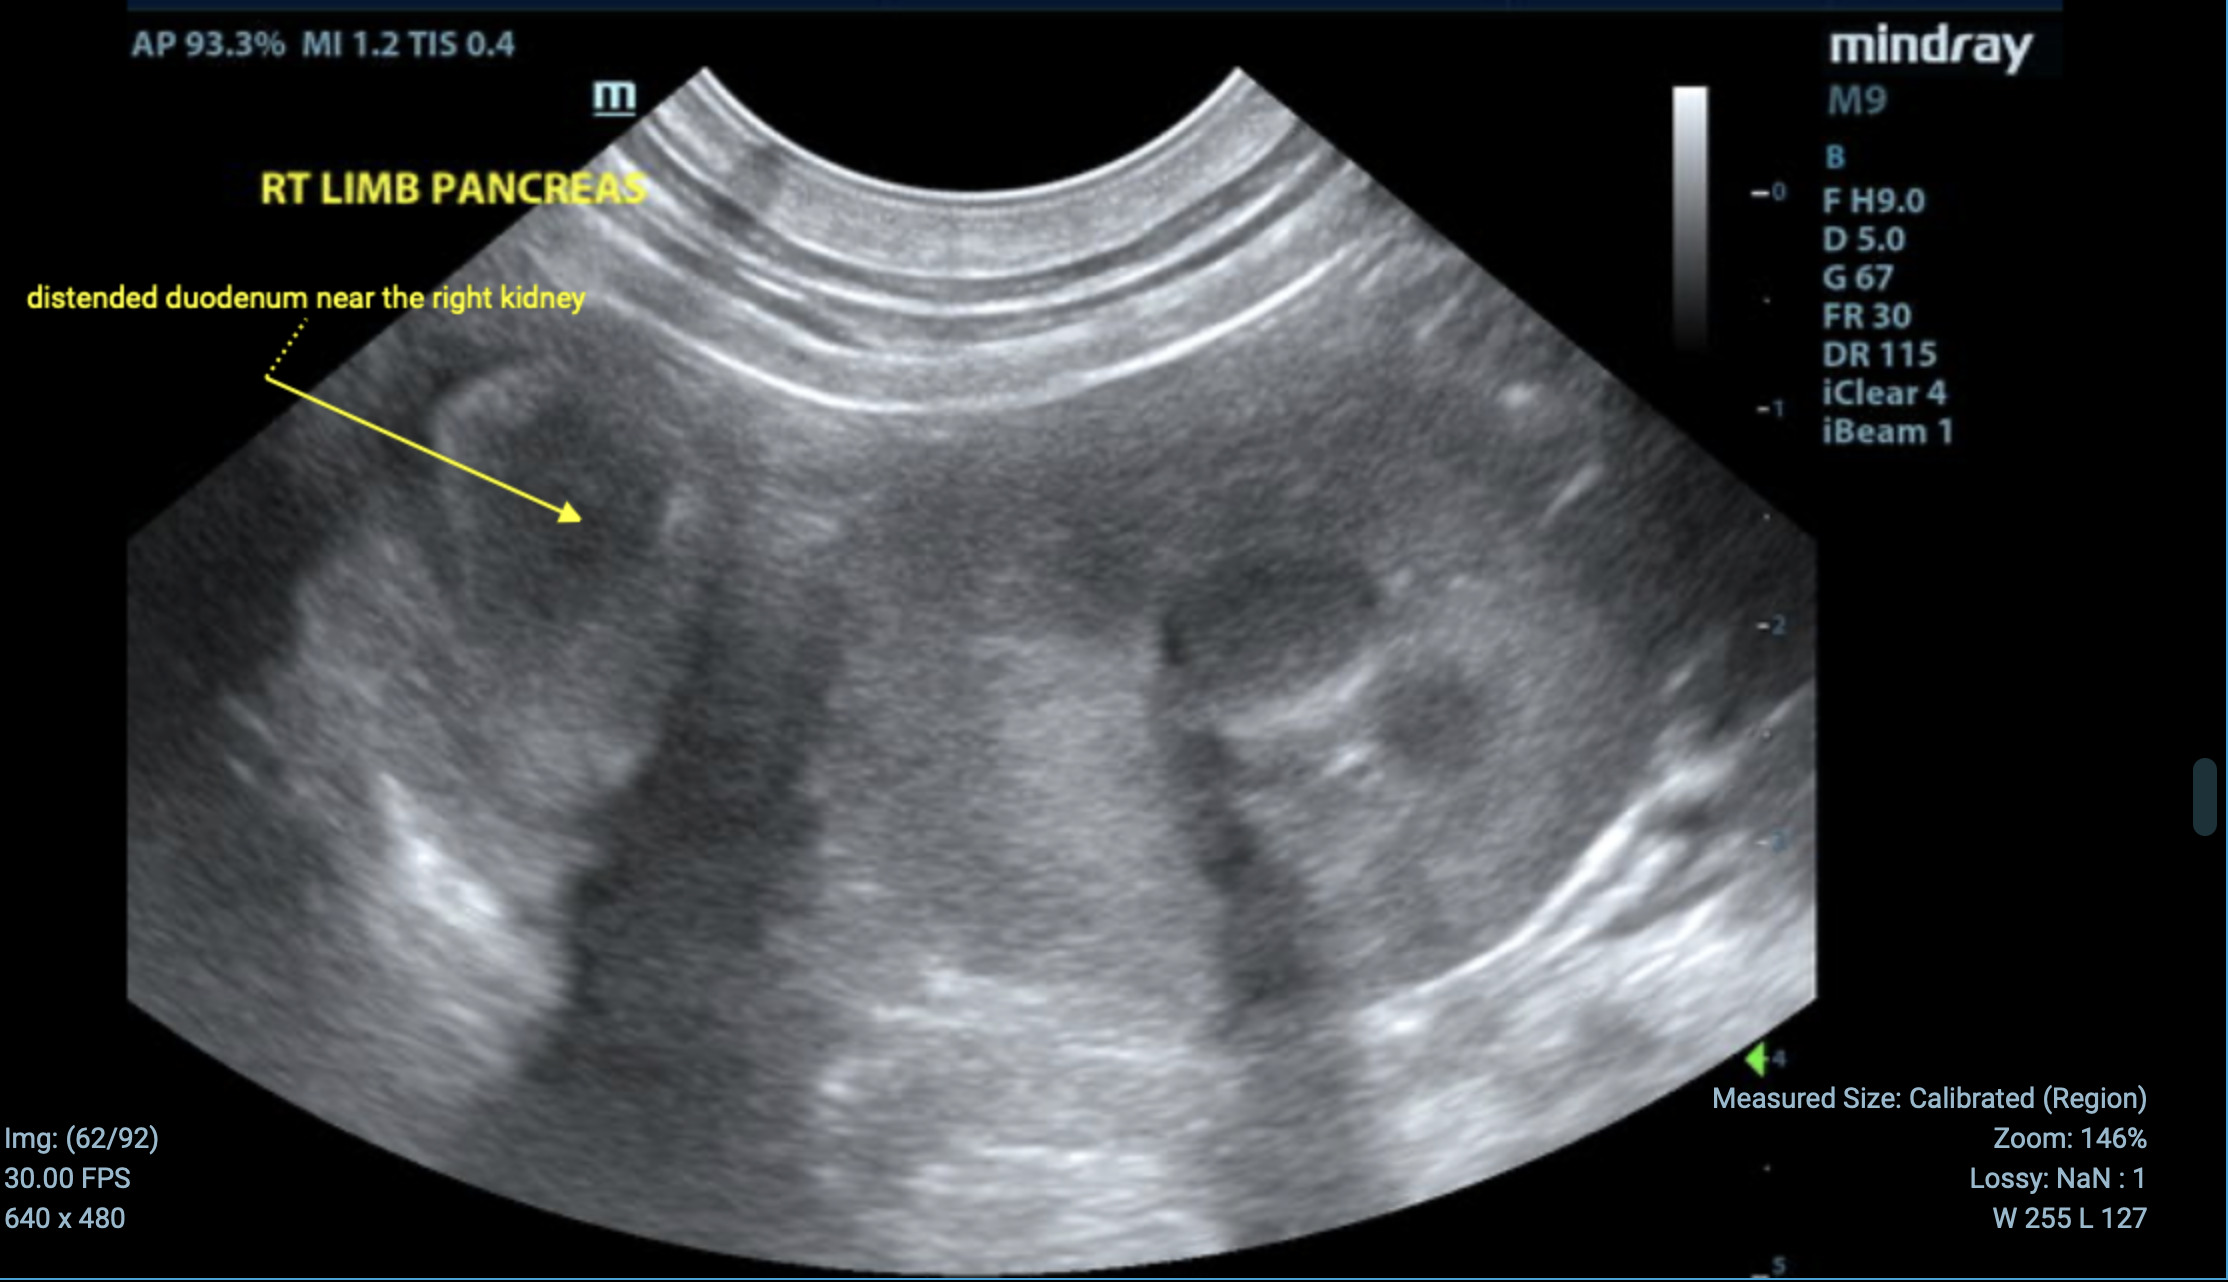

In the video below, Dr. Fred Gromalak, DVM is going to through an emergency “foreign body hunt” using ultrasound images obtained by SVS Imaging Mobile Sonographer Kim Liedberg. This live demonstration shows how we identify and assess possible obstructions.

Next, we turn our attention to the small intestine. In this particular case, we notice small intestinal luminal dilation, which can be a sign of a potential obstruction.

After reviewing all the structures and imaging, we notice a segment of the small intestine that stands out due to its dilation and suspicious appearance. While we don’t see clear evidence of a foreign body in this segment, the combination of luminal dilation, regional inflammation, and wall thickening raises strong suspicion for a foreign object blocking the intestine.